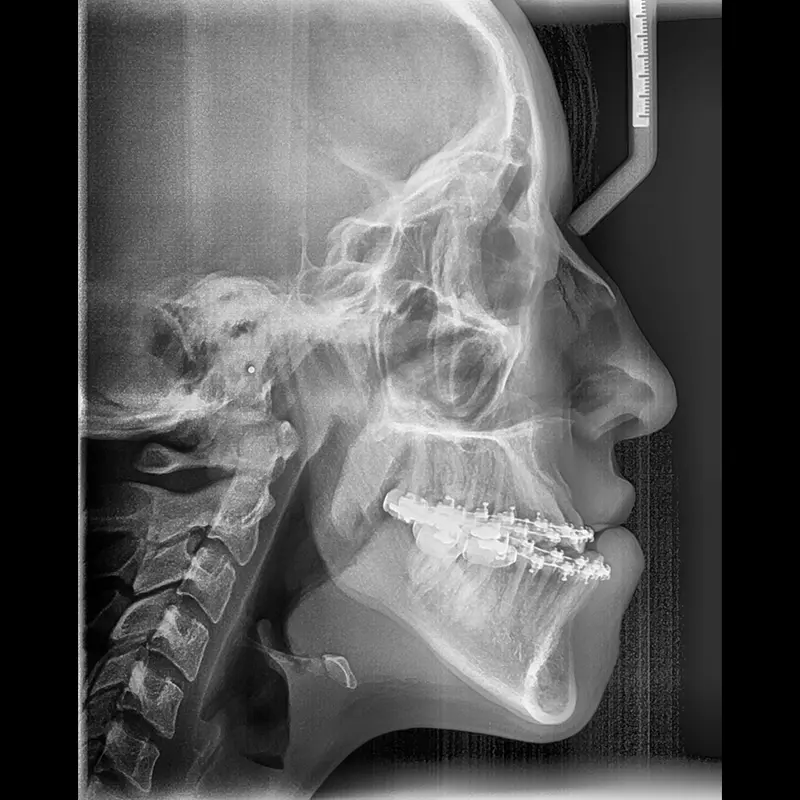

Cirugía ortognática (asimetrías faciales)

Corrección quirúrgica de deformidades óseas en mandíbula y maxilares para mejorar estética, mordida y respiración.

La cirugía ortognática, del griego orthos, «recto» y gnathos, «mandíbula», es una intervención quirúrgica que se encarga de corregir las deformidades dento-craneo-maxilofaciales mediante movimientos óseos maxilares y mandibulares, para lograr el equilibrio perfecto entre todas las características faciales del paciente.

Este tipo de alteraciones faciales aparecen en la fase de crecimiento de los pacientes, se estabilizan al final de la misma, y pueden causar problemas como apnea del sueño, trastornos de la ATM, problemas de maloclusión o falta de armonía esquelética, entre otros.